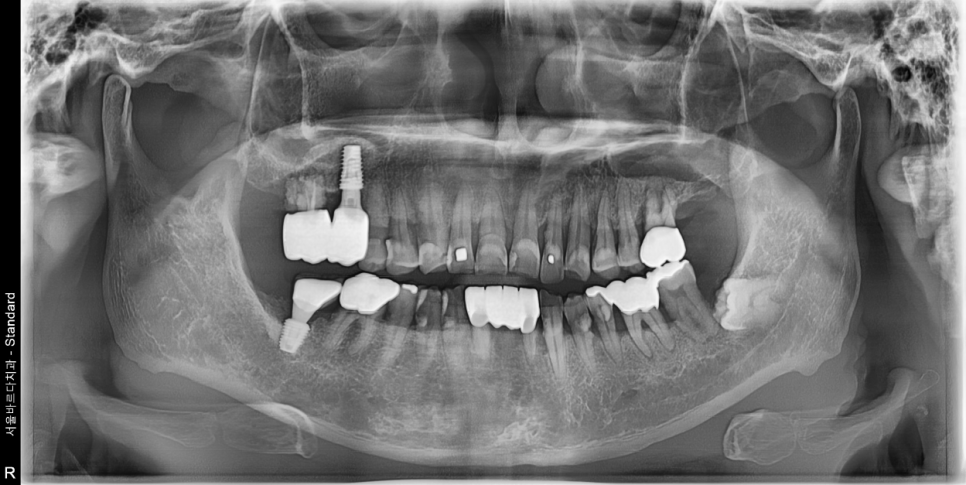

치아의 전반적인 뼈와 치아상태를 확인하는 파노라마 엑스레이 촬영해보니

오른쪽 위 어금니와 아래 앞니 뿌리끝에 염증도 보이고

전체적으로 잇몸 하방에 치석이 많이 있었습니다.

정확하고 안전한 자리에 계획한 대로 임플란트가 이쁘게 들어간것을 볼수 있습니다.

임플란트 픽스처 주변과 위쪽으로 뼈이식이 동그랗게

잘 되어 있는 것도 볼 수 있습니다.